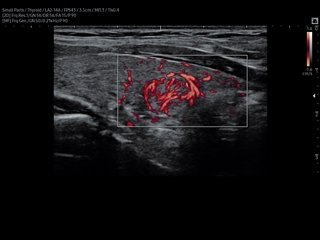

V7. Thyroid, S-Flow.